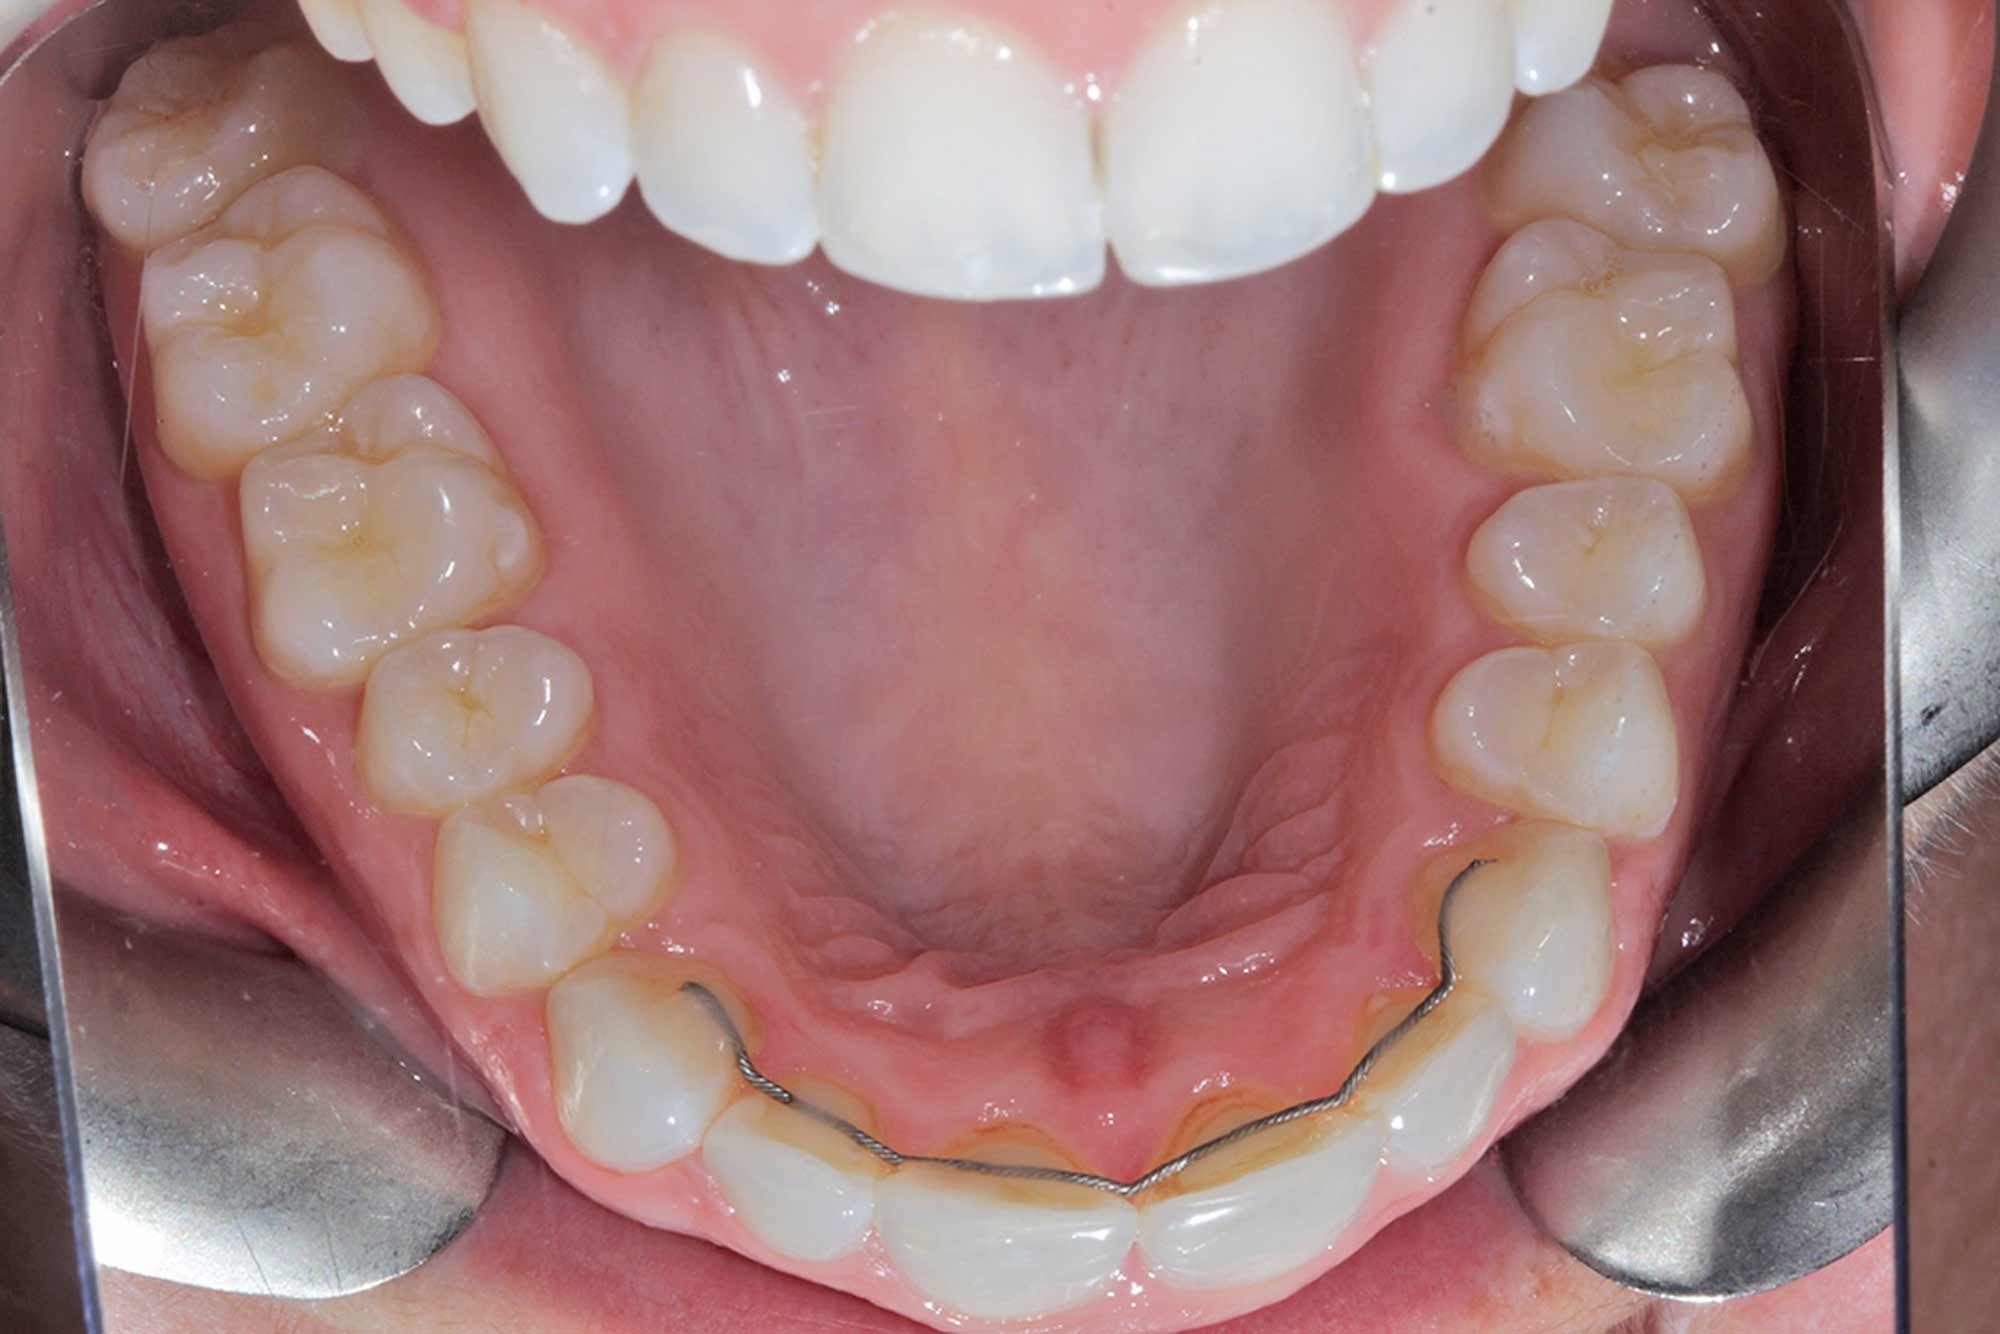

In this case, 14 aligners were needed to achieve the outcome we were looking for. This was followed by two short stages of refinements, as we certainly aimed for perfection in the end result and strived to match the original Clincheck prediction.

Once the tooth positioning and colour were both at an exemplary stage, it was time to frame the result with composite direct edge bonding. This has been made much easier due to all the other factors. Our restorative material of choice for this case was Venus Pearl shade BL. This matched the patient’s newly whitened teeth perfectly.

The other factors had been carried out to such a high level, that the bonding stage was very straightforward and fairly easy to conduct. Using the right tools to blend the margins in and polish them to give this case even more longevity in the long run. The key to these cases is anatomy. Match the anatomy and proportions, and it will blend beautifully.